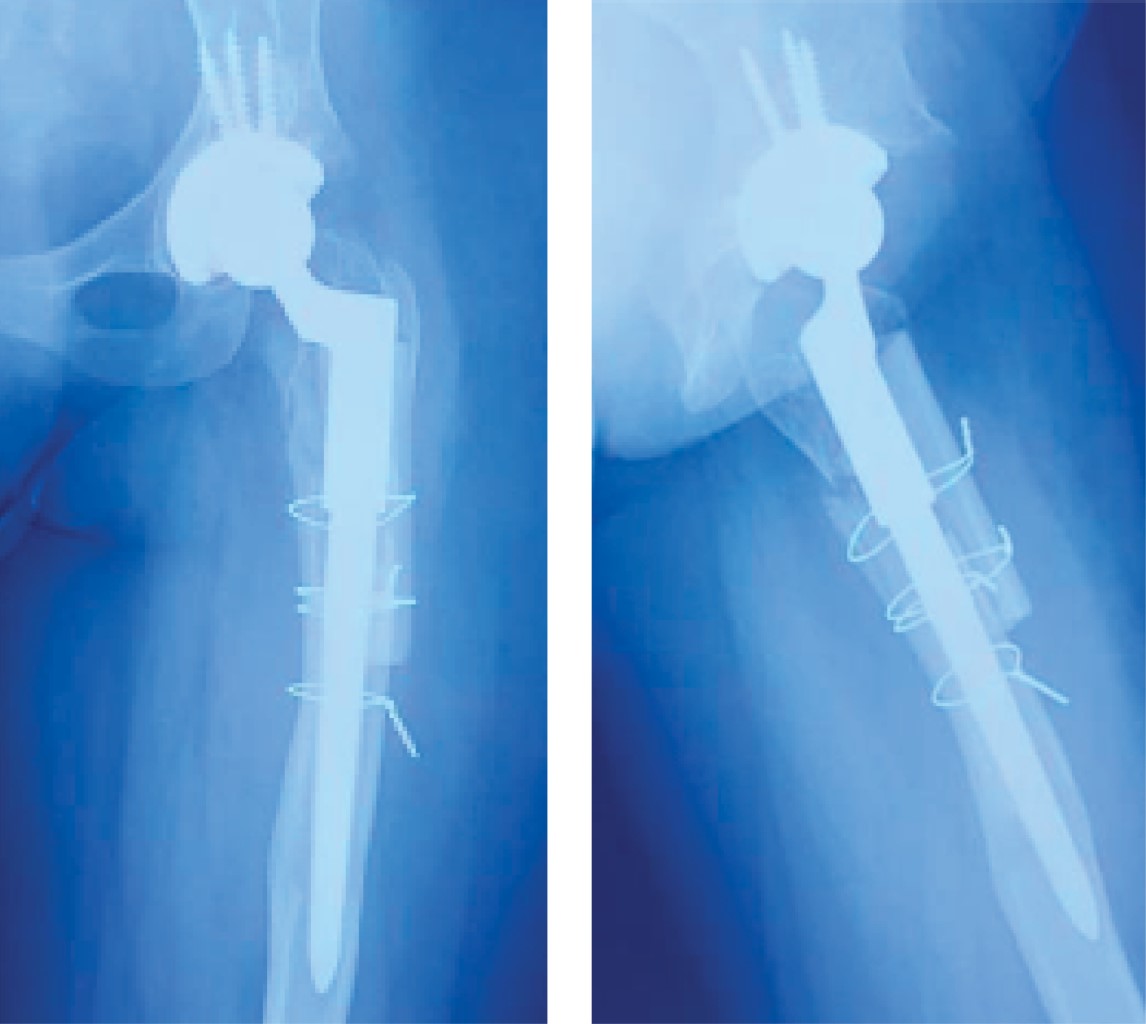

Se decide realizar revisión protésica de cadera bajo consentimiento de paciente en 2019 a sus 24 años, se retira copa acetabular, se realiza osteotomía femoral extendida y se retira vástago, se coloca copa acetabular con 45o de inclinación acetabular y 10o de anteversión, en fémur se coloca vástago modular cónico estriado más colocación de tabla de aloinjerto de diáfisis femoral fijándolo mediante cerclaje (Figura 4). En la actualidad, la paciente tiene 26 años, dos años de postoperada con ausencia de dolor y con una función de su extremidad inferior que le ha permitido regresar a realizar sus actividades diarias, así como el inicio de actividad física deportiva, de esta manera mejorando su calidad de vida, se refiere satisfecha con el resultado de su cirugía.

En lo que respecta al fémur, presenta un defecto proximal que se extiende a la diáfisis, el vástago indicado inicialmente no fue el correcto presentando hundimiento del mismo, ya que estos tipo de fémur presentan su anatomía irregular y son biomecánicamente insuficientes para una fijación metafisaria proximal, se decide retirar vástago realizando una osteotomía lateral femoral extendida, colocando un vástago modular cónico estriado, los cuales son los idóneos para este tipo defectos, ya que presentan una fijación diafisaria distal, donde al menos se requieren de 2 cm para que sean estables, otorgándoles estabilidad axial y rotacional.19 Se colocan tablas de aloinjerto diafisarias en defecto femoral proximal con la finalidad de proporcionar soporte estructural disminuyendo el índice de fracturas periprotésicas, así como la no unión de la osteotomía femoral extendida.20

Figura 4